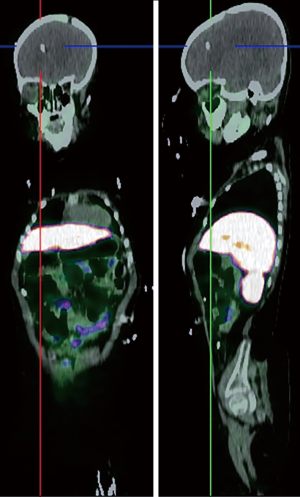

Somatostatin is a neuropeptide released by endocrine cells, neurons, and immune cells which its functions include neuroregulation (sensory, motor, and cognition) and cell growth inhibition by paracrine and autocrine pathways (37,38). Somatostatin works through a group of transmembrane G protein-coupled receptors that enter the cell following binding to specific ligands (39). So far, six subtypes of somatostatin receptors (SSTRs) are discovered including SSTR 1, 2A, 2B, 3, 4, and 5. A broad spectrum of brain tumors express different subtypes of SSTR on their surface including frequent primary brain tumors e.g., gliomas and meningiomas, pediatric brain tumors (medulloblastomas), pituitary adenomas, and supratentorial primitive neuroendocrine tumors (PNETs) (40-43). Dutour and colleague (44) have shown that gliomas and meningiomas, as the first and second most common primary brain tumors, are positive for different subtypes of SSTR. It was demonstrated that although all of them have at least one SSTR subtype, many of these harboring multiple SSTR subtypes. They provided proofs on detecting SSTRs in both tumors and their surrounding tissues, particularly blood vessels. Concerning gliomas, low-grade gliomas (WHO grade I, II) depicted higher expression levels compared to high-grade gliomas (WHO grade III, IV) (45). To date, three 68Ga-DOTA peptides are developed for clinical imaging comprised of 68Ga-DOTA-TOC, 68Ga-DOTA-NOC, and 68Ga-DOTA-TATE. The shared property of these 68Ga-DOTA peptides is the ability in binding to SSTR2, and they differ with regard to their SSTR subtype affinity and profile (Figures 4,5).

Meningioma is the second most frequent primary brain tumor and is benign in 90% of cases. The current standard imaging modality in diagnosis is conventional MR imaging (43). Although the SSTR receptors are positive in the healthy leptomeningeal cell, the meningioma cells express higher levels of them (46,47). Afshar-Oromieh et al. (48) aimed to compare the ability in detecting meningioma lesions between 68Ga-DOTA-peptide PET/CT and contrast-enhanced MRI (CE-MRI) within a total of 134 patient. They revealed that 68Ga-68Ga-DOTA-peptide PET/CT has higher accuracy compared to CE-MRI in meningioma detection (190 vs. 171). The investigators concluded that 68Ga-DOTA-peptide PET/CT could play a complementary role with MRI in cases where MRI finding has failed in definitive diagnosis or lake of feasibility for biopsy. Another promising potential of 68Ga-DOTA-peptide PET/CT was reported by Milker-Zabel and colleagues (49) through a study that showed target volume delineation using 68Ga-DOTA-PET/CT and MRI in comparison to CT or MRI alone has changed the radiotherapy planning in 73% of 26 patients. Gehler et al. (50) reported similar results as well. One example of this modality in meningioma is illustrated in Figure 6.